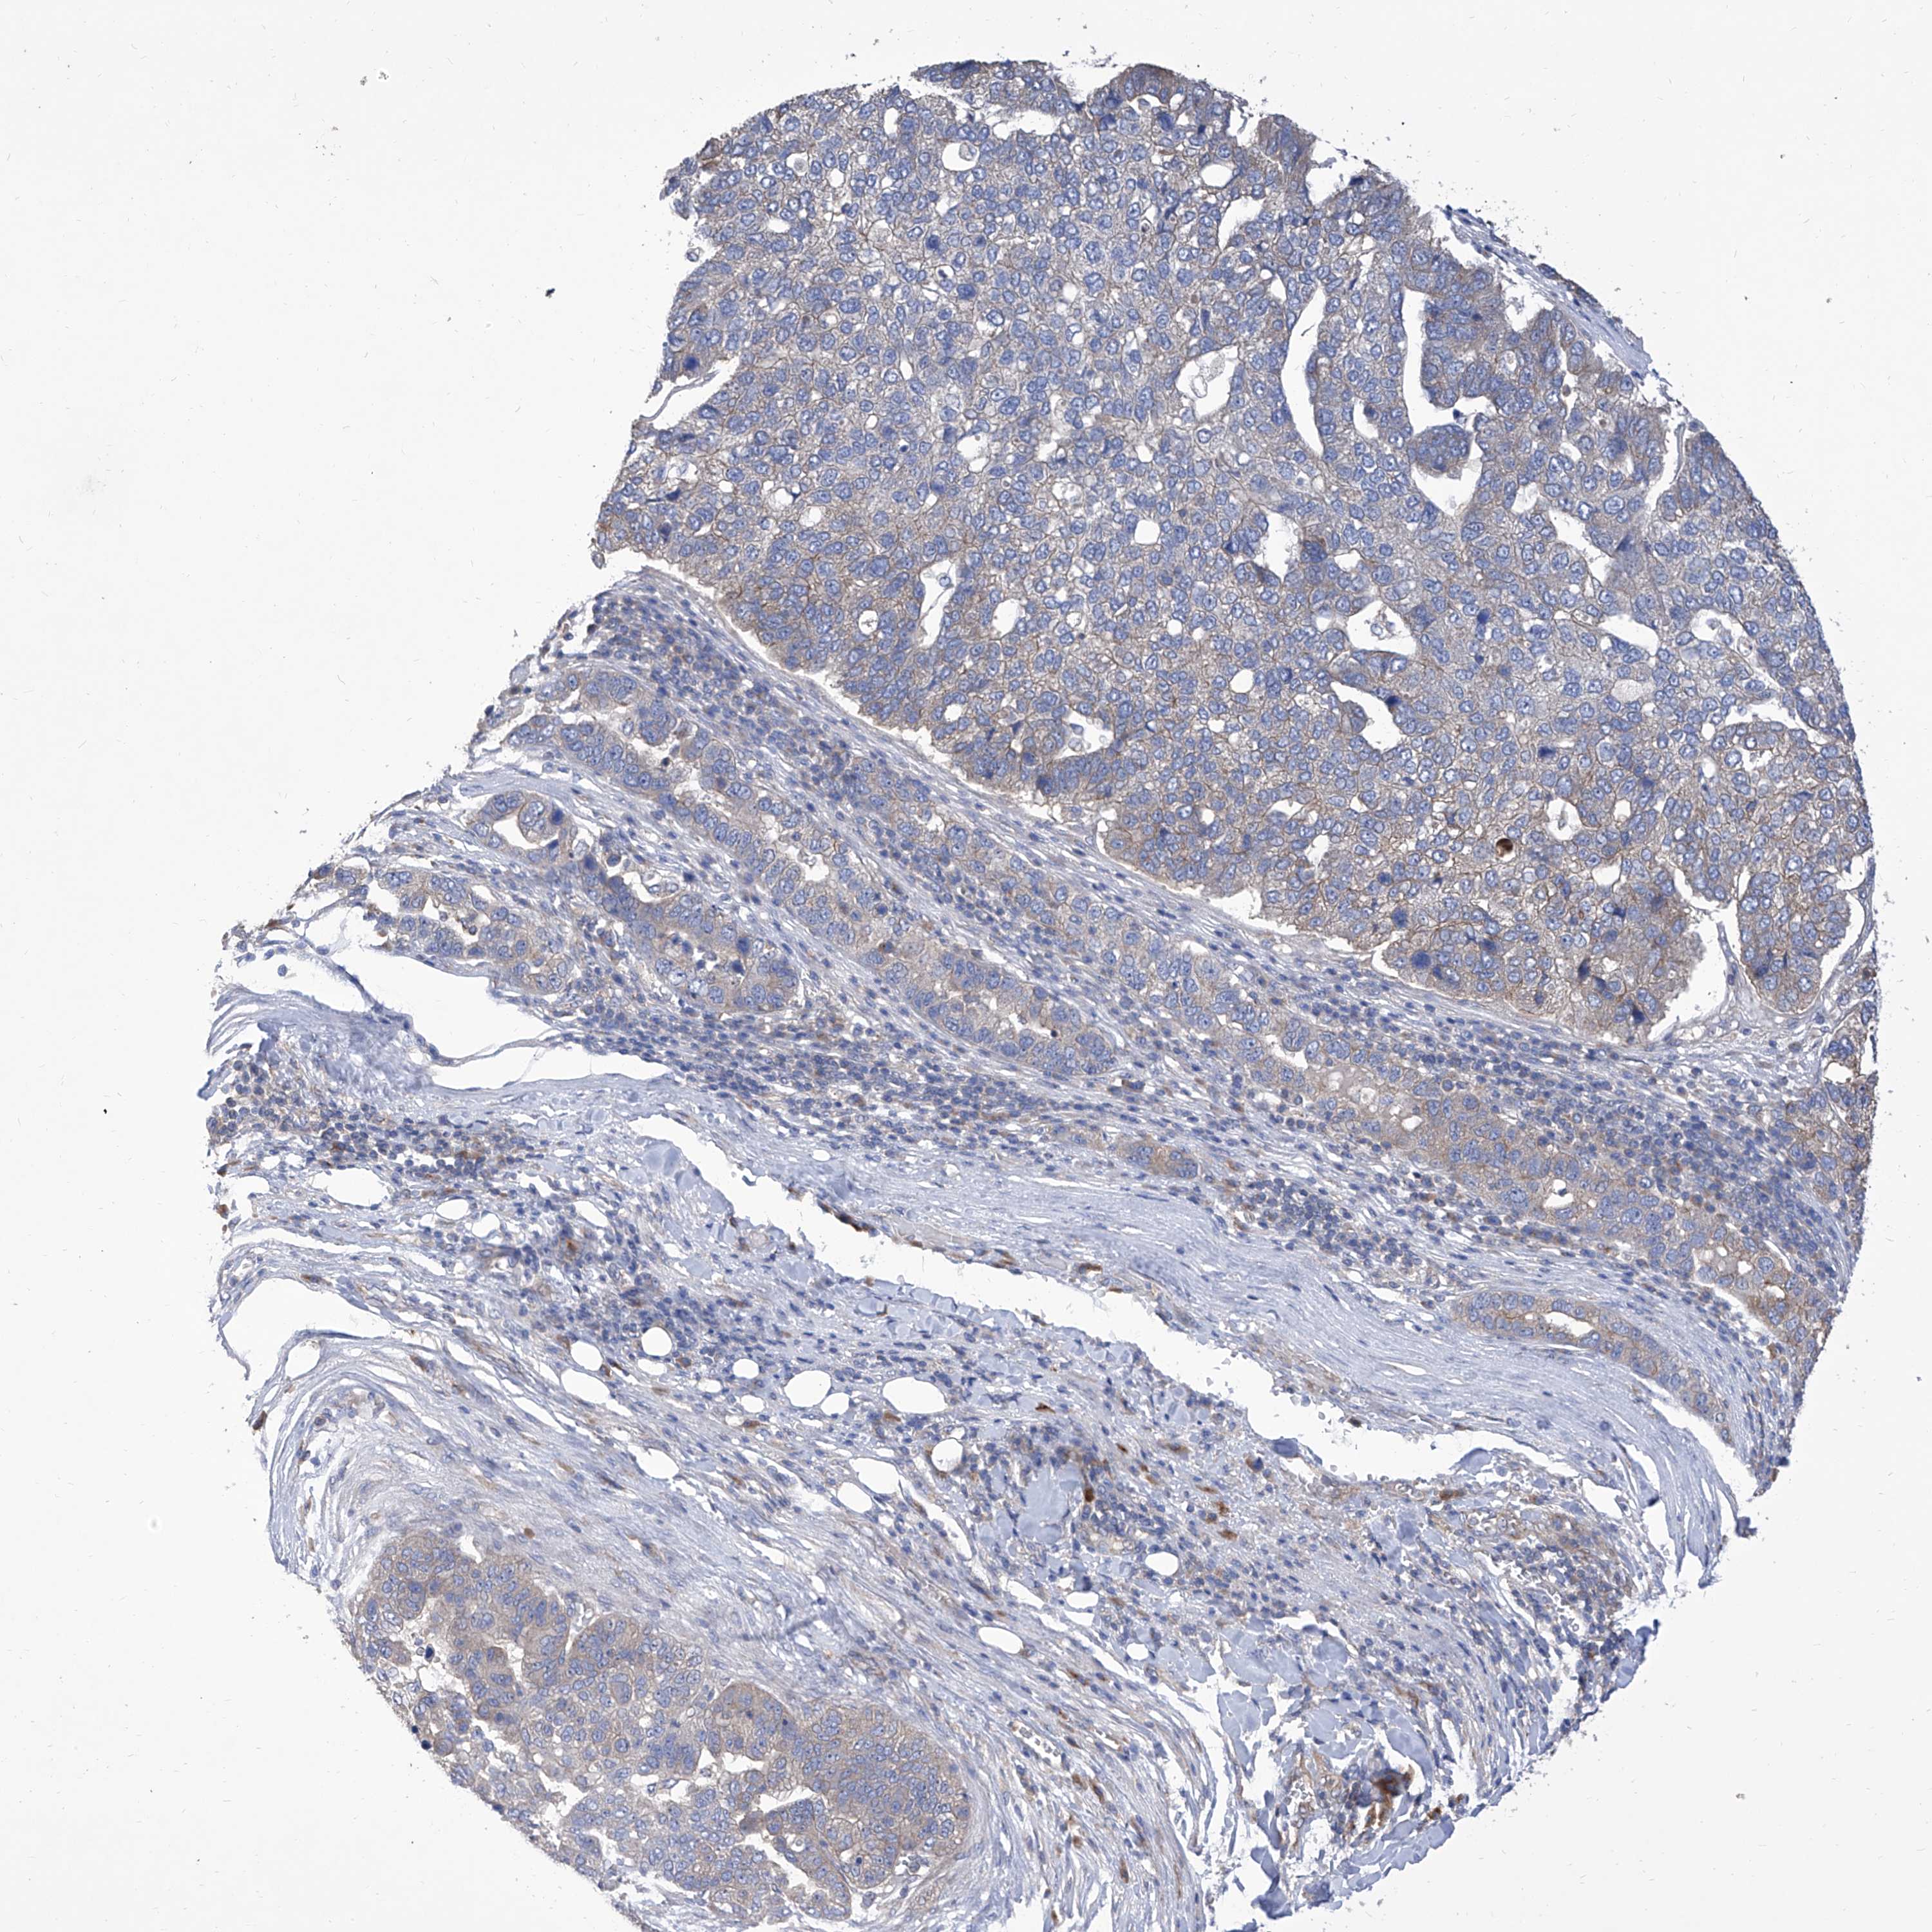

PANCREATIC CANCER - Protein expressioni

A mouse-over function shows sample information and annotation data. Click on an image to view it in a full screen mode. Samples can be filtered based on level of antibody staining by selecting one or several of the following categories: high, medium, low and not detected. The assay and annotation is described here.

Note that samples used for immunohistochemistry by the Human Protein Atlas do not correspond to samples in the TCGA dataset.

Antibody stainingi

Antibody staining in the annotated cell types in the current human tissue is reported as not detected, low, medium, or high, based on conventional immunohistochemistry profiling in selected tissues. This score is based on the combination of the staining intensity and fraction of stained cells.

Each image is clickable and will lead to virtual microscopy that enables deeper exploration of all samples and also displays staining intensity scores, fraction scores and subcellular localization as well as patient and tissue information for each sample.

Antibody HPA030164

Antibody HPA030165

Antibody HPA030166

Adenocarcinoma, NOS